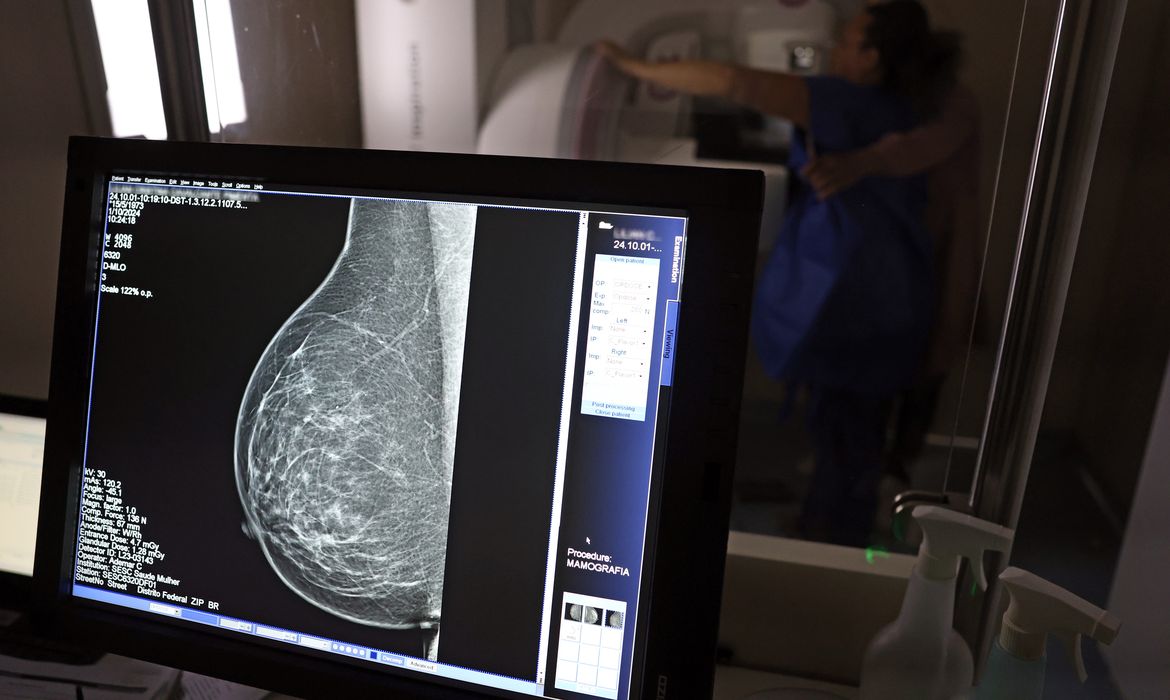

O Ministério da Saúde passou a recomendar o acesso a mamografia, via Sistema Único de Saúde (SUS), para mulheres de 40 a 49 anos – mesmo que não haja sinais ou sintomas de câncer de mama. De acordo com a pasta, a faixa etária concentra 23% dos casos da doença, e a detecção precoce aumenta as chances de cura. Até então, a orientação era que o exame fosse feito a partir dos 50 anos. A medida faz parte de um conjunto de ações anunciadas nesta terça-feira (23) voltado para a melhoria do diagnóstico e da assistência. A recomendação para mulheres a partir dos 40 anos é que o exame seja feito sob demanda, em decisão conjunta com o profissional de saúde. “A paciente deve ser orientada sobre os benefícios e desvantagens de fazer o rastreamento. Mulheres nesta idade tinham dificuldade com o exame na rede pública de saúde por conta da avaliação de histórico familiar ou necessidade de já apresentar sintomas”, informou o ministério em nota. As mamografias via SUS em pacientes com menos de 50 anos, de acordo com a pasta, representam 30% do total, o equivalente a mais de 1 milhão apenas no ano de 2024. Rastreamento ativo Outra medida anunciada é a ampliação da faixa etária para o rastreamento ativo – quando a mamografia é solicitada de forma preventiva a cada dois anos. A idade limite, até então, era 69 anos. Agora, passa a ser 74 anos. Dados do ministério revelam que quase 60% dos casos de câncer de mama estão concentrados entre 50 e 74 anos. “A ampliação do acesso à mamografia aproxima o Brasil de práticas internacionais, como as adotadas na Austrália, e reforça o compromisso em garantir diagnóstico precoce e cuidado integral às mulheres brasileiras. O câncer de mama é o mais comum e o que mais mata mulheres, com 37 mil casos por ano”, reforçou a pasta. Os números mostram que, em 2024, cerca de 4 milhões de mamografias para rastreamento e 376,7 mil exames diagnósticos foram realizados no SUS.   O ministro da Saúde, Alexandre Padilha, durante anúncio de recomendações para mamografia no SUS - Foto: Marcelo Camargo/Agência Brasil Unidades móveis O ministério anunciou ainda a oferta de 27 carretas de saúde da mulher em 22 estados por meio do programa Agora Tem Especialistas. A ação é voltada para a expansão do acesso a consultas, exames e cirurgias com o objetivo de reduzir o tempo de espera para atendimento no SUS. Os primeiros testes foram realizados em Goiânia. No próximo mês, as carretas seguem para diferentes estados do país. A expectativa é alcançar até 120 mil atendimentos ao longo de outubro, com investimento de R$ 18 milhões para a execução da ação. “As unidades móveis vão oferecer uma ampla gama de serviços para o diagnóstico precoce de câncer de mama e de colo do útero, incluindo mamografia, ultrassonografia, punção e biópsia de mama, colposcopia e consultas médicas presenciais e por telemedicina”, informou a pasta. Biópsia Outra iniciativa é a aquisição de 60 kits de biópsia, cada um com uma mesa de biópsia estereotática em decúbito ventral e um equipamento de raio-X especializado. Os equipamentos, segundo ministério, utilizam tecnologia de imagem 2D e 3D, garantindo maior precisão diagnóstica e reduzindo a necessidade de repetição de procedimentos. Medicamentos mais modernos A partir de outubro, o SUS vai disponibilizar também novos medicamentos para o tratamento do câncer de mama. Um deles é o trastuzumabe entansina, indicado para mulheres que ainda apresentam sinais da doença mesmo após a primeira fase do tratamento com quimioterapia antes da cirurgia. Outro grupo de medicamentos inclui os inibidores de ciclinas (abemaciclibe, palbociclibe e ribociclibe), recomendados para pacientes com câncer de mama avançado ou metastático – quando a doença já se espalhou para outras partes do corpo – e que têm receptor hormonal positivo e negativo. Relacionadas Câncer de mama: manifestação cobra acesso a tratamento aprovado no SUS Câncer de mama: uma em cada três pacientes tem menos de 50 anos Planos devem estimular mamografias para receber atestado de qualidade